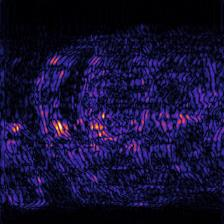

Recently, deep neural networks have greatly advanced undersampled Magnetic Resonance Image (MRI) reconstruction, wherein most studies follow the one-anatomy-one-network fashion, i.e., each expert network is trained and evaluated for a specific anatomy. Apart from inefficiency in training multiple independent models, such convention ignores the shared de-aliasing knowledge across various anatomies which can benefit each other. To explore the shared knowledge, one naive way is to combine all the data from various anatomies to train an all-round network. Unfortunately, despite the existence of the shared de-aliasing knowledge, we reveal that the exclusive knowledge across different anatomies can deteriorate specific reconstruction targets, yielding overall performance degradation. Observing this, in this study, we present a novel deep MRI reconstruction framework with both anatomy-shared and anatomy-specific parameterized learners, aiming to "seek common ground while reserving differences" across different anatomies.Particularly, the primary anatomy-shared learners are exposed to different anatomies to model flourishing shared knowledge, while the efficient anatomy-specific learners are trained with their target anatomy for exclusive knowledge. Four different implementations of anatomy-specific learners are presented and explored on the top of our framework in two MRI reconstruction networks. Comprehensive experiments on brain, knee and cardiac MRI datasets demonstrate that three of these learners are able to enhance reconstruction performance via multiple anatomy collaborative learning.